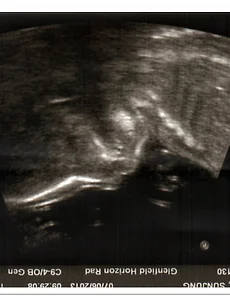

뉴질랜드 생활/다민, Damin's102 기다림. 2013. 6. 17. 남자는 남자끼리.. 요즘 다현이가 자주 하는 말입니다. '남자는 남자끼리' 샤워할 때, 잠잘 때, 놀 때.. 모두 남자는 남자끼리 해야한다고 합니다. 우리집에 남자가 한명 더 생기게 되었습니다. 예상을 깨고 금동이가 남자아이라고 초음파 검사 결과를 받았습니다. 엄마 아빠 모두 여자아이가 태어나길 바랬.. 2013. 6. 7. 금동이 초음파 사진. 4월 18일. 금동이 13주차 4일째. 초음파 찍으러 다녀왔습니다. 다현이 때보다 약간 흥분됨이 덜한게 미안할 뿐입니다.ㅎㅎ 임신을 한 후 출산 할 때까지 특별한 이유가 없다면 3번의 초음파 촬영이 있습니다. 오늘이 그 중 처음입니다. 12주가 지나서 처음이고, 20주가 지난 후 한번 더 그리고.. 2013. 4. 18. 이전 1 ··· 9 10 11 12 다음